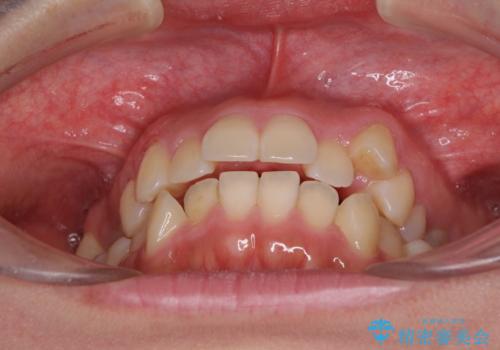

- 八重歯と前歯のデコボコを気にして来院された患者様です。

八重歯の他に、上顎歯列を狭窄しているという問題点がありました。

また、八重歯により上顎奥歯が前方に位置しており、咬み合わせの改善も必要な状況でした。

八重歯の動きが鈍く、治療期間は長期化しました。

癒着の疑いもありましたが、アンカースクリューを多用し、何とか改善することができました。